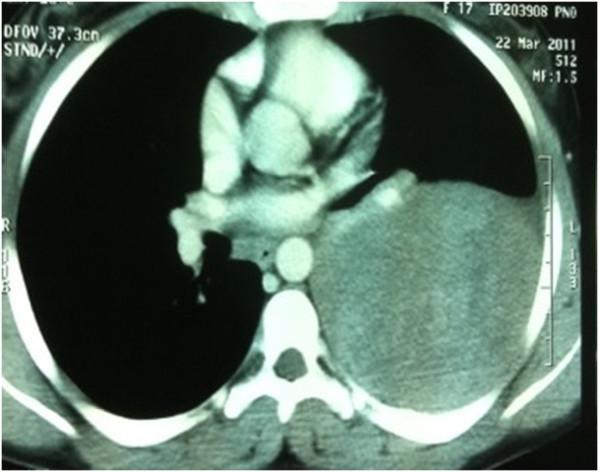

Askin's tumor is a primitive neuroectodermal tumor developing from the soft tissues of the chest wall. Its diagnosis approach is complex and requires a multidisciplinary team. Given the rarity of this entity, no regimen has been validated in the literature. We report two cases of Askin's tumor with a major response to polychemotherapy and surgical resection in one case. These cases show that treatment of Askin's tumor should be multimodal, requiring discussion in multidisciplinary tumor working groups.

Askin's tumor: a case report and literature review.